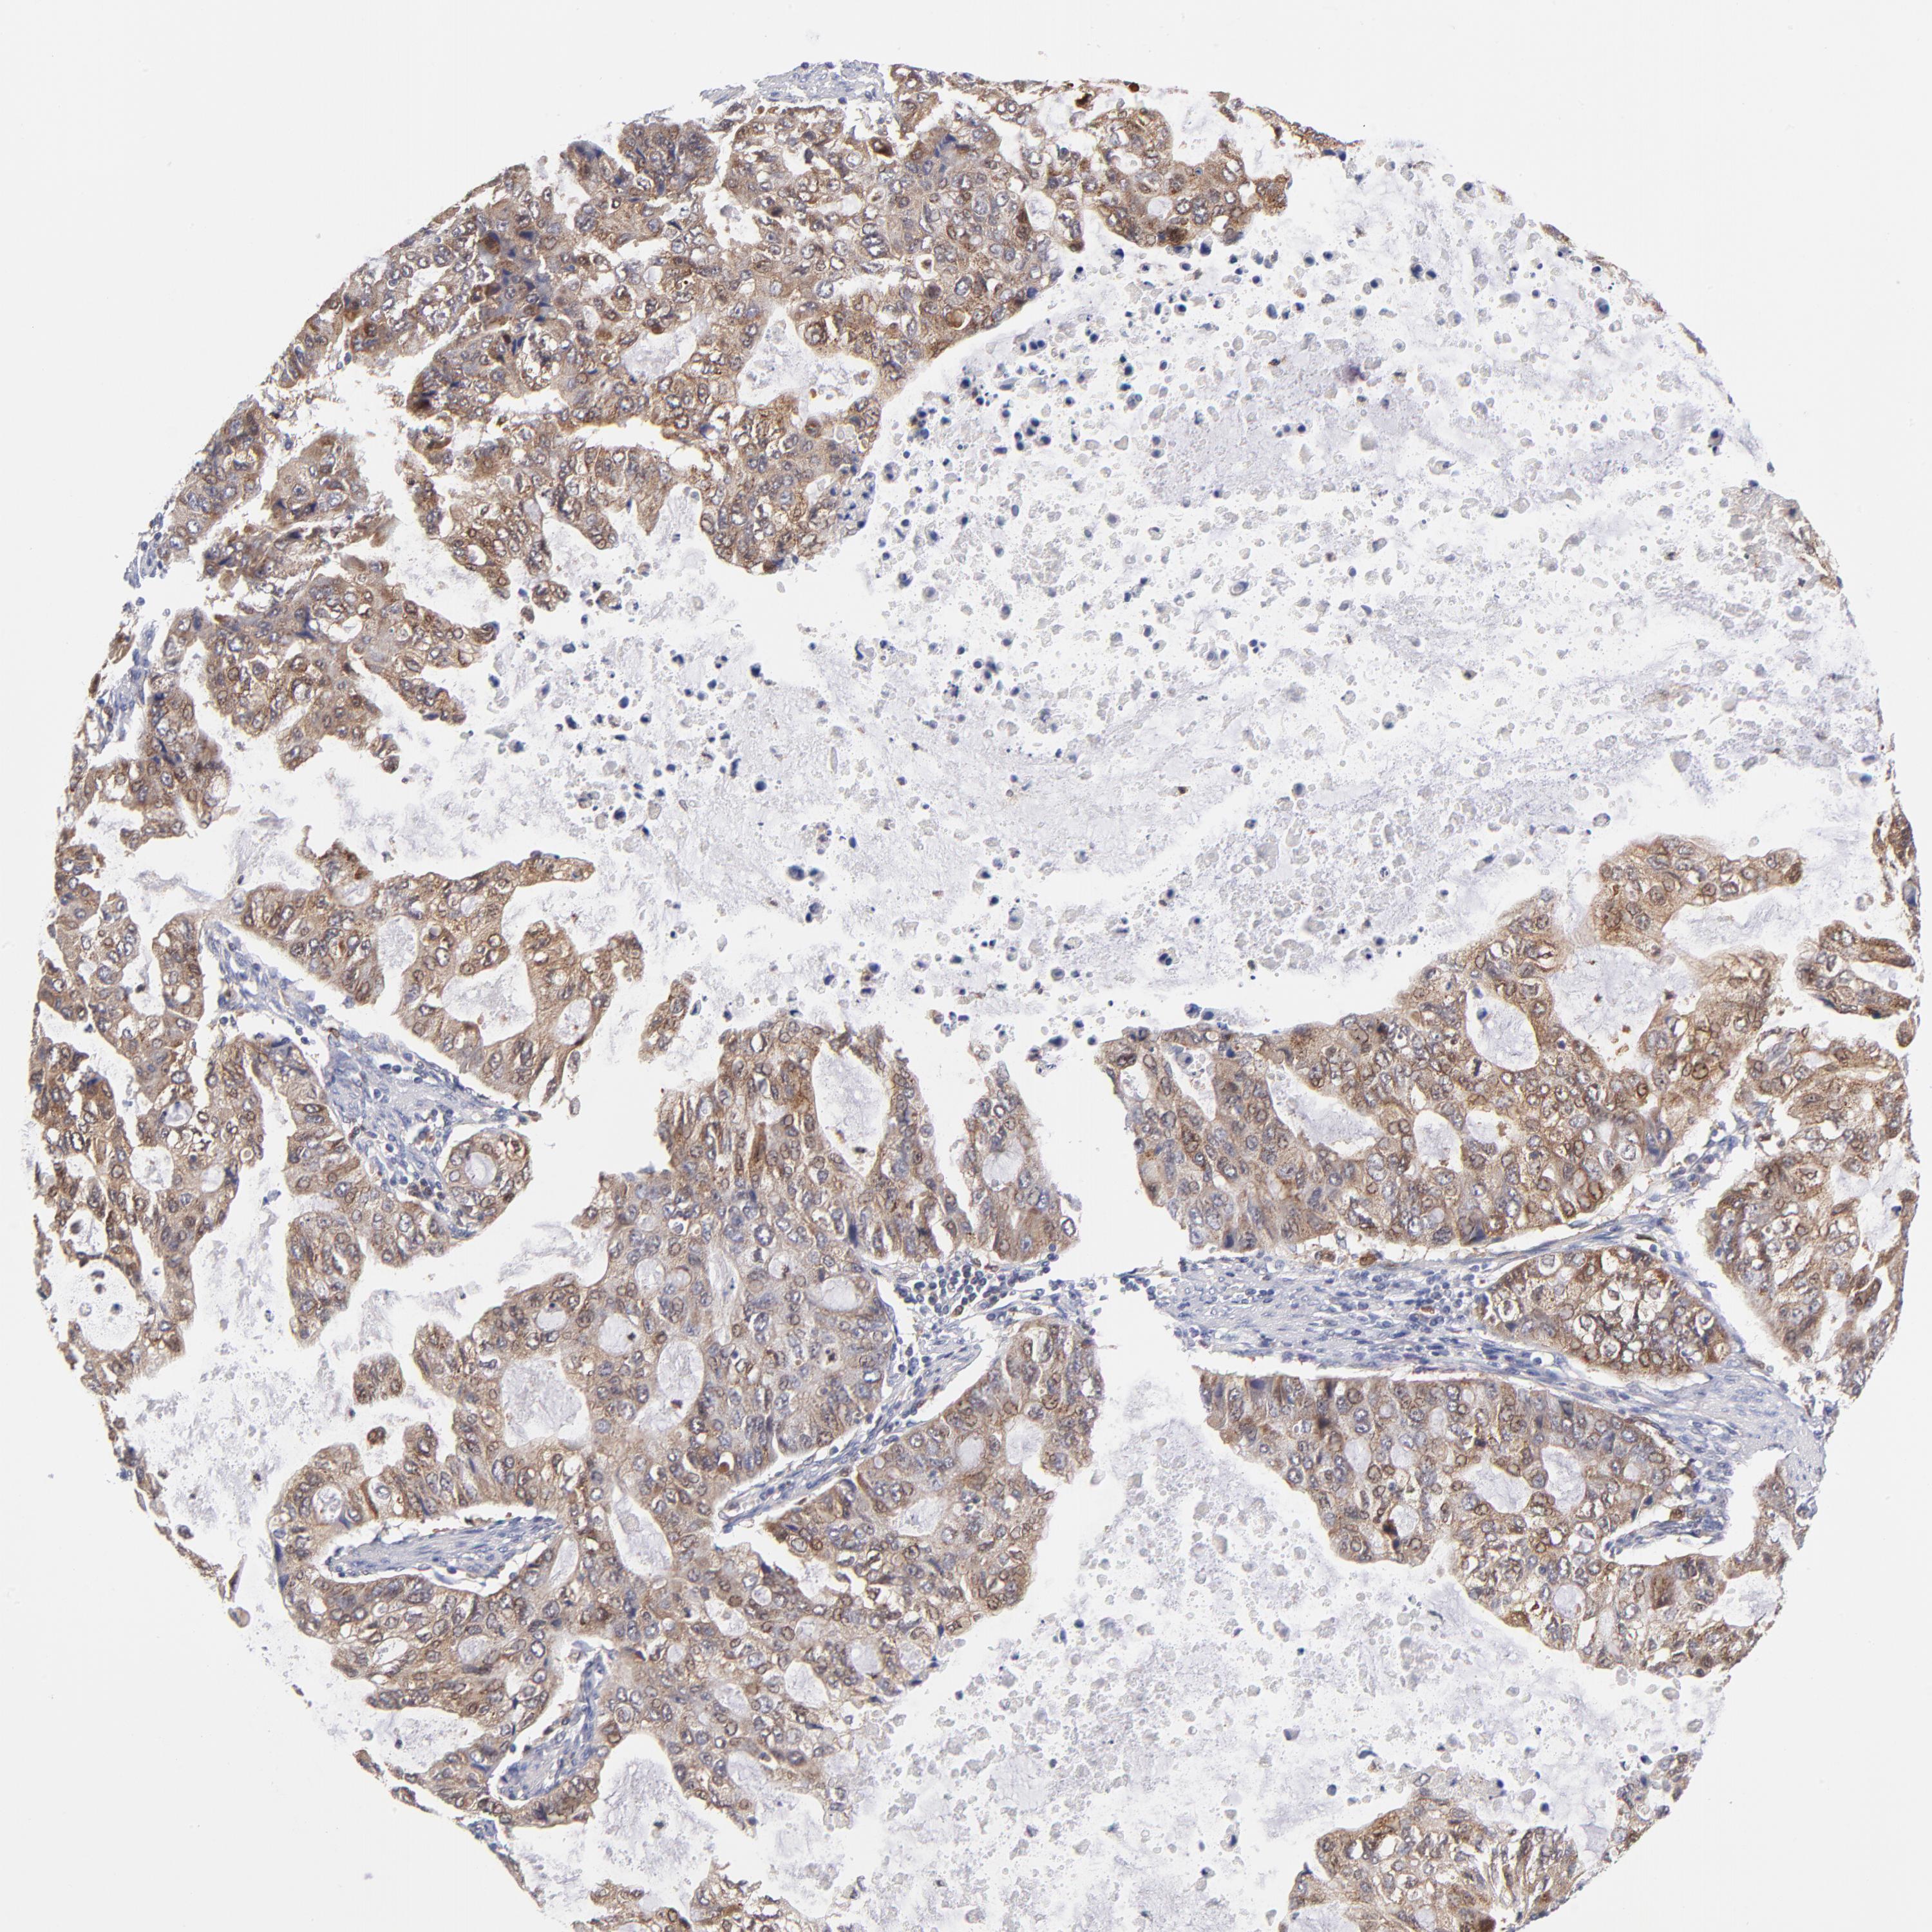

STOMACH CANCER - Protein expressioni

A mouse-over function shows sample information and annotation data. Click on an image to view it in a full screen mode. Samples can be filtered based on level of antibody staining by selecting one or several of the following categories: high, medium, low and not detected. The assay and annotation is described here.

Antibody stainingi

Antibody staining in the annotated cell types in the current human tissue is reported as not detected, low, medium, or high, based on conventional immunohistochemistry profiling in selected tissues. This score is based on the combination of the staining intensity and fraction of stained cells.

Each image is clickable and will lead to virtual microscopy that enables deeper exploration of all samples and also displays staining intensity scores, fraction scores and subcellular localization as well as patient and tissue information for each sample.

Antibody HPA000722

Antibody CAB003771

Staining

High

Medium

Low

Not detected

Intensity

Strong

Moderate

Weak

Negative

Quantity

>75%

75%-25%

<25%

None

Location

Nuclear

Cytoplasmic/membranous

Cytoplasmic/membranous,nuclear

Adenocarcinoma, NOS